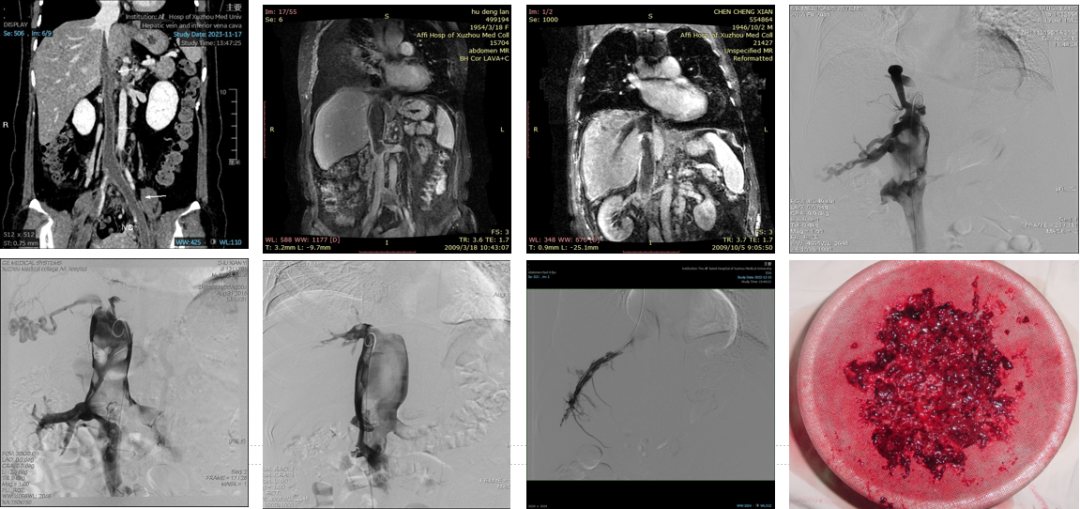

疑难病例处理--下腔静脉再造

男,24岁,8岁时3楼跌下肝脏碎裂,三次手术止血将下腔静脉结扎,20岁后出现

右下肢静脉曲张,色素沉着伴踝部溃疡不愈合,术前MRI提示下腔静脉肝后段消失

02

疑难之处:肝、下腔静脉阻塞合并血栓形成(N=542)

疑难病例:下腔静脉血栓形成的处理--留置导管溶栓